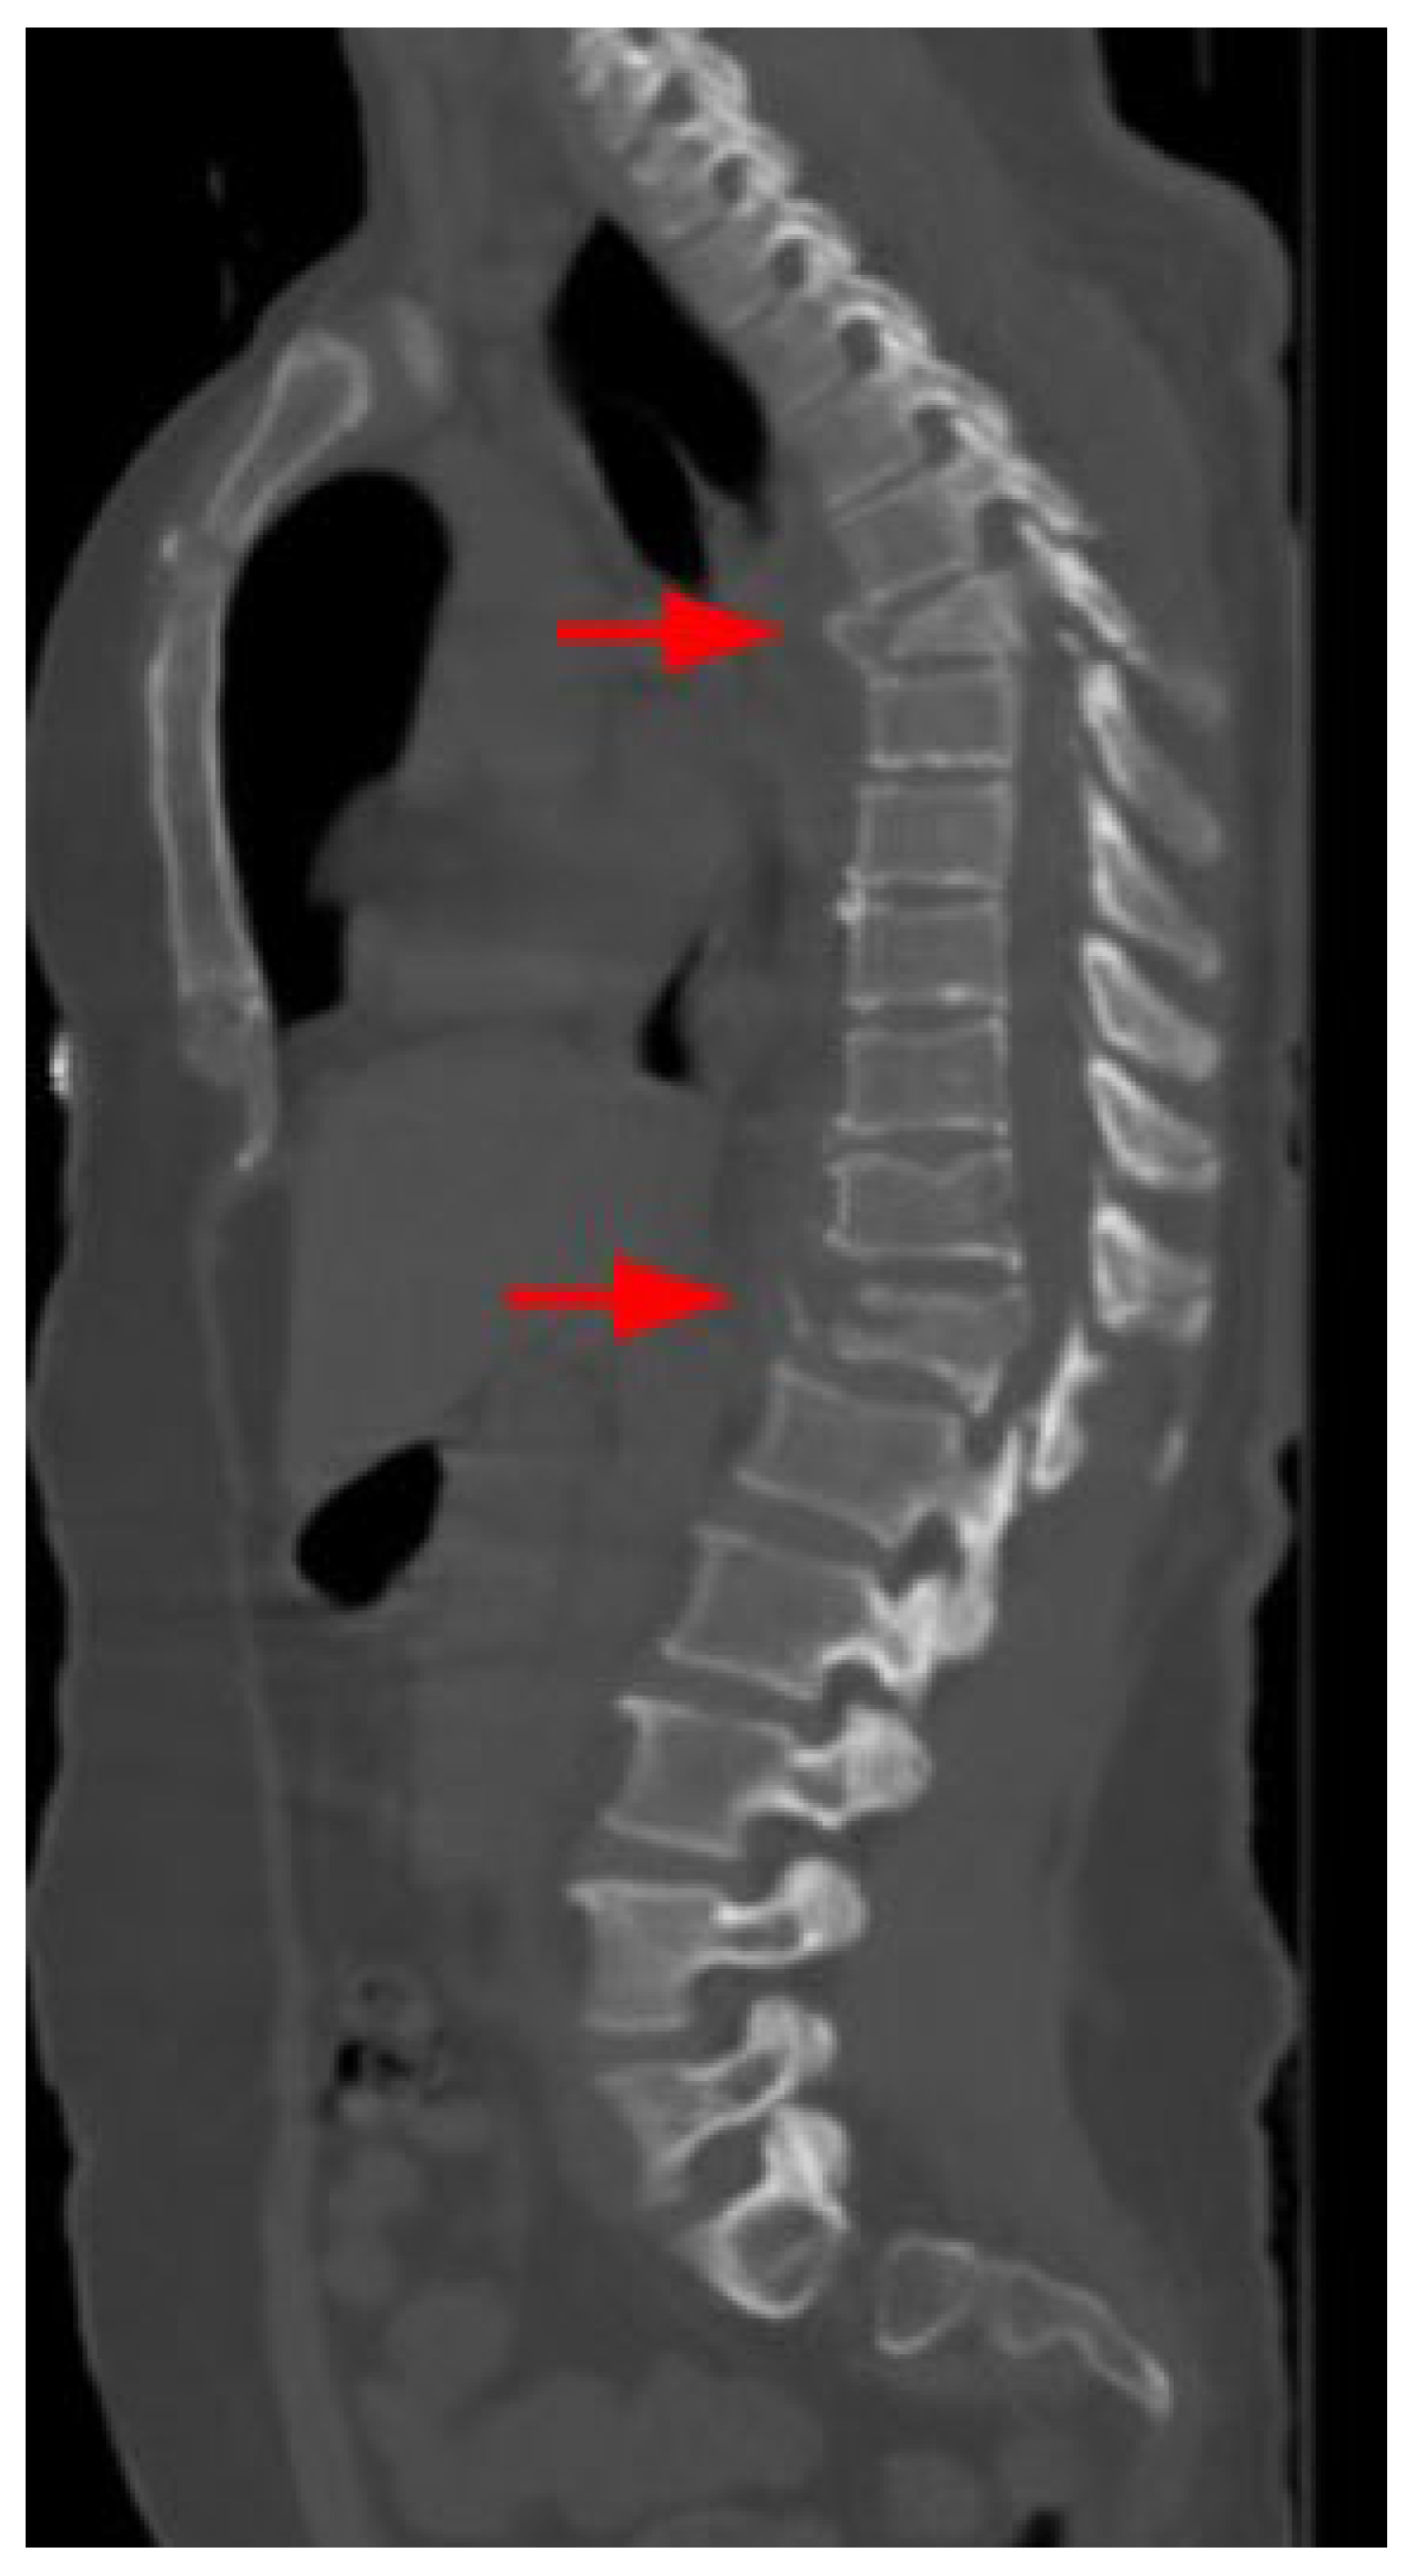

| Vertebra | 3 (15.8) | 16 (84.2) | 49 (34.8) | 92 (65.2) | 52 (32.5) | 108 (67.5) | 0.098 |